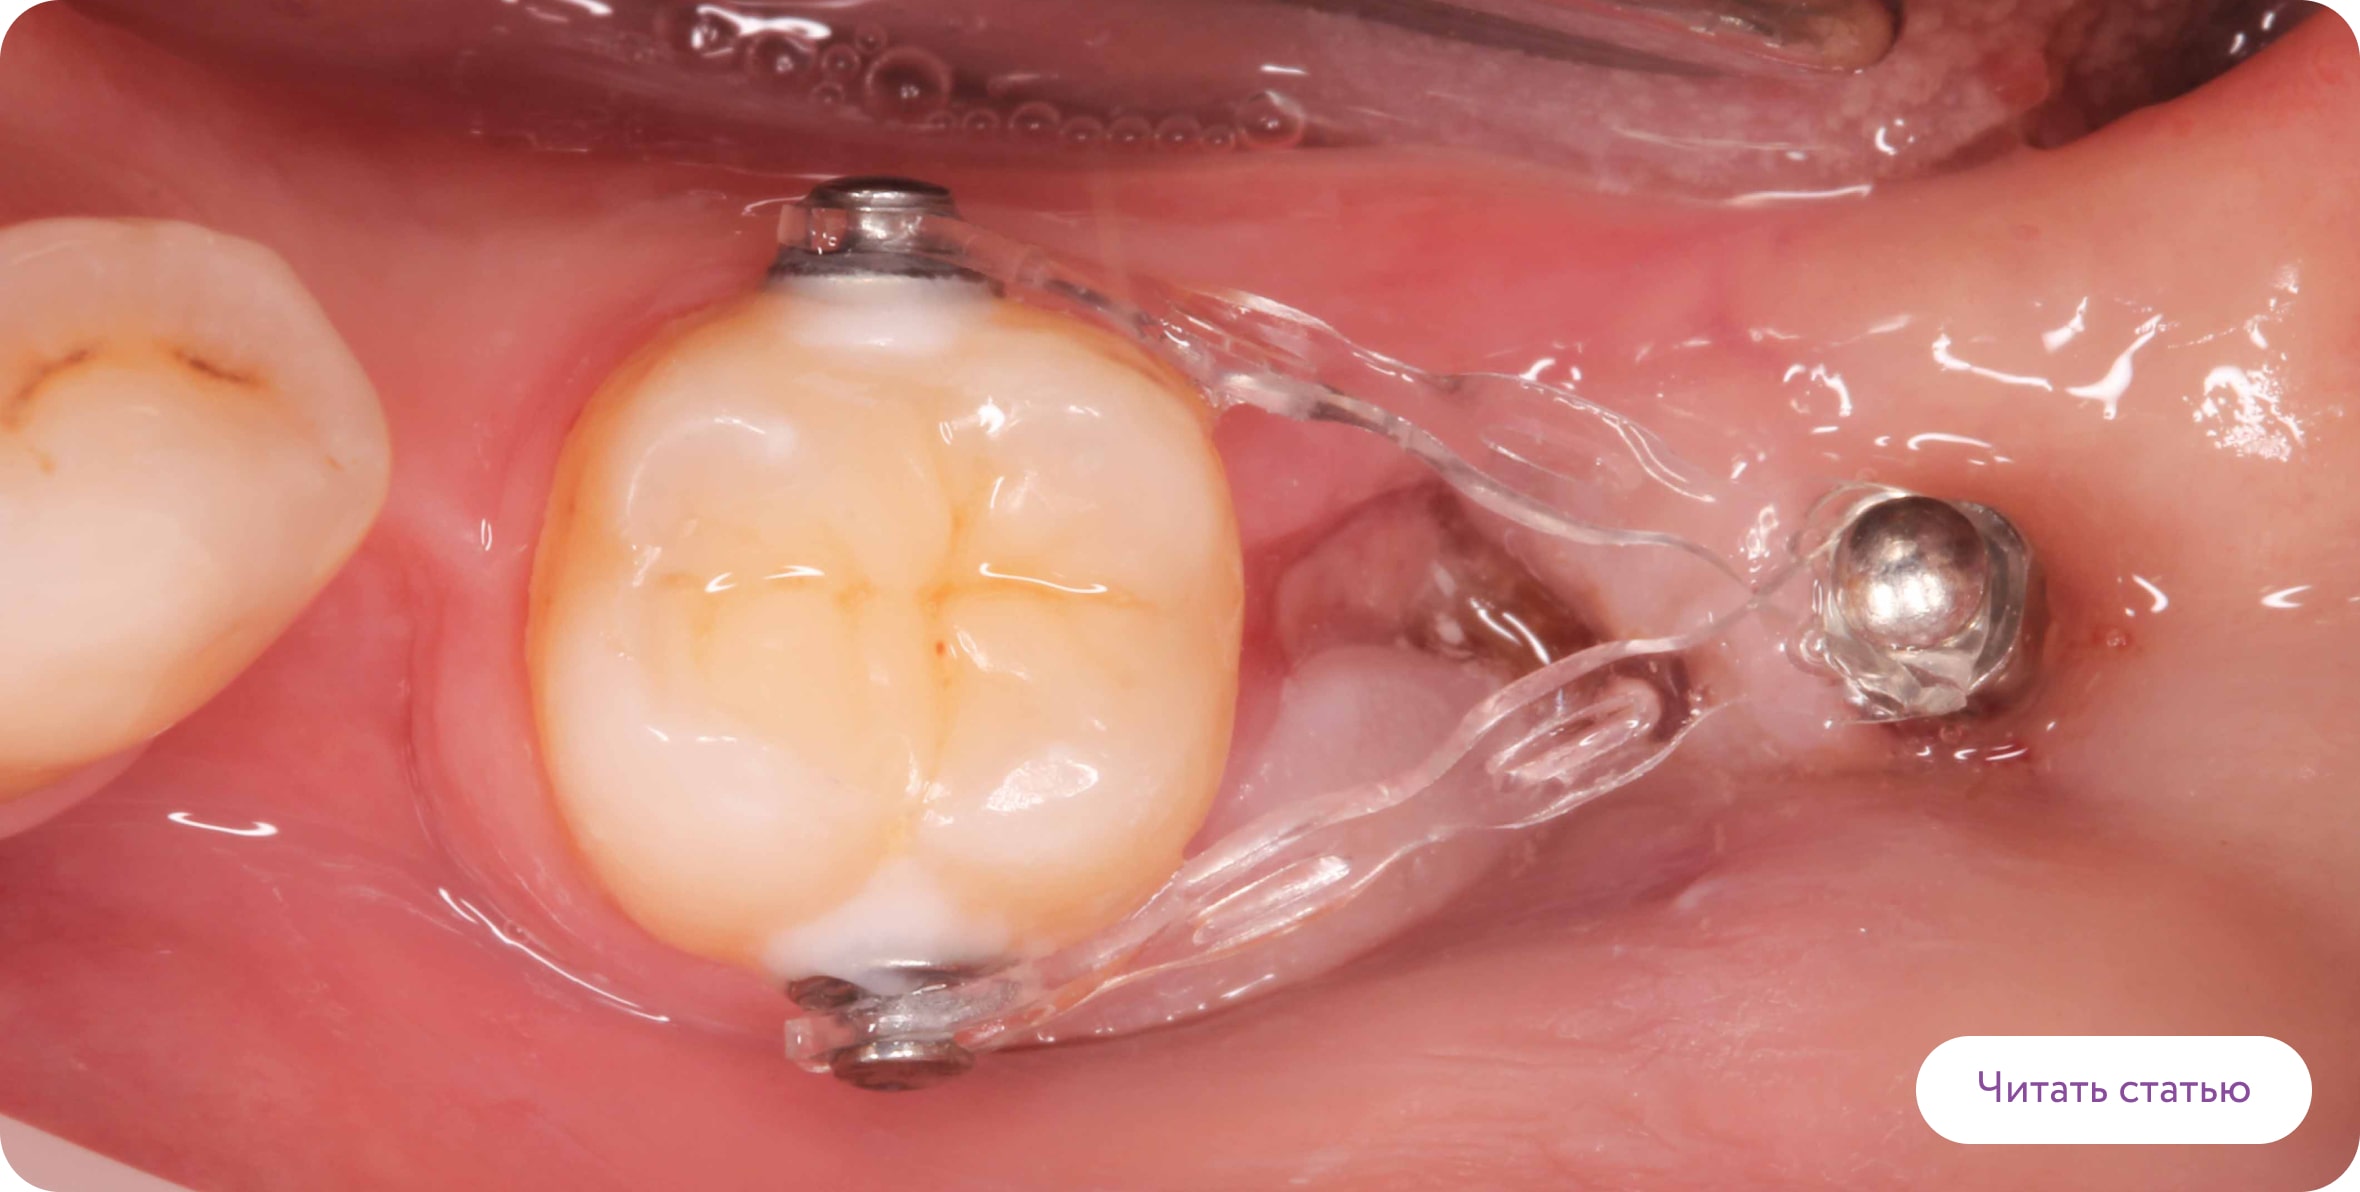

Ортодонтические мини-винты

Ортодонтические мини-винты используются как дополнительная опора для перемещения зубов. Винты устанавливаются временно в кость между зубами на 3-6 месяцев